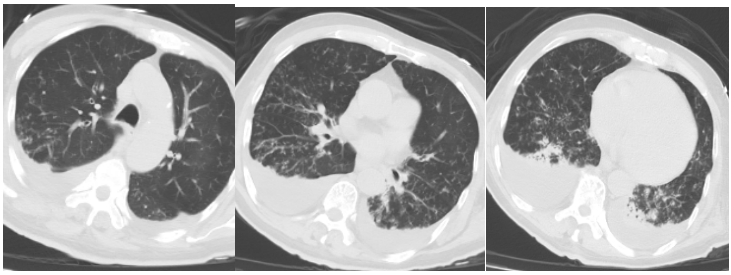

10月9日胸部CT(图2):两肺感染性病变。慢支肺气肿改变。两侧胸腔积液伴相邻肺组织膨胀不全心脏增大,心包少量积液主动脉壁局部钙化气管插管术后气管痰液黏附可能食管壁稍增厚。

图片

2  CT2025-10-09